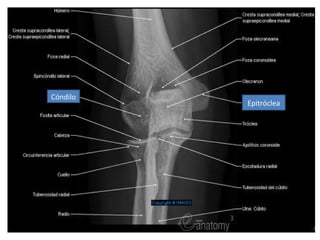

Cóndilo

Epitróclea

Cóndilo Epitróclea